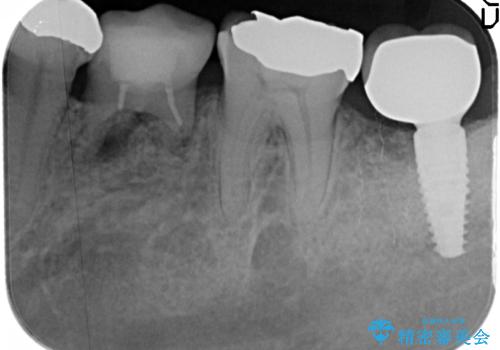

[前歯 セラミック治療] すぐに前歯が取れる きちんと治療して欲しい

- 他院で前歯の治療を繰り返し行うものの、クラウン・コアの脱離が頻回に起きやり直しのない治療を求めて来院されました。

脱離により感染のうかがわれる根管内は再根管治療を行い、ラバーダムを行い防湿下でファイバーコア築盛を行うことで脱離への抵抗性を高めます。

歯肉縁上の歯質が少ない場合脱離や破折リスクが高まるためコアの丁寧な築盛や綿密な咬合調整が必要です。